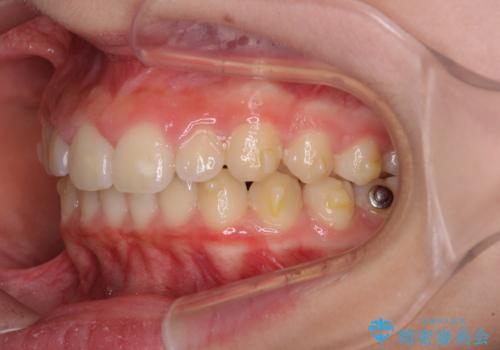

- ヨーロッパにてインビザライン矯正を始めたものの、日本に転居することになり、治療の継続を希望して来院された患者様です。

治療計画に無理がなく、現地担当医と速やかに連絡が取れるとのことで、インビザライン社での転医手続きを行い、継続して治療を行うこととしました。

舌の突出癖により、上下前歯が非接触となっていたため、トレーニングを徹底的に指導し、安定した咬み合わせにより終了させることができました。